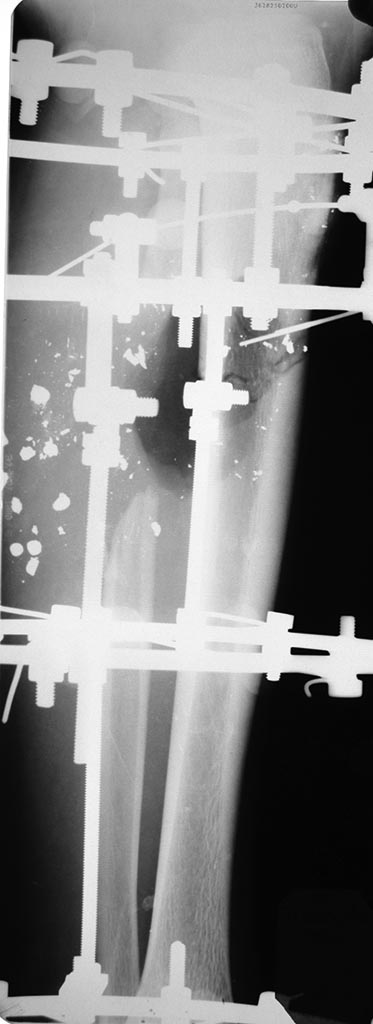

[Ortho] огнестрельное ранение голени

Добавляю рентген